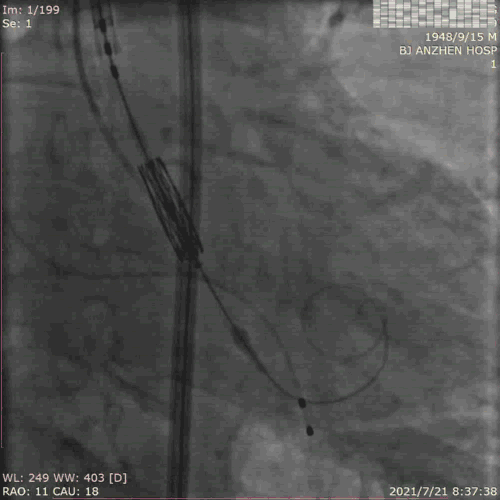

PCI过程:术中使用 7F AL 0.75 Guiding,顺利于RCA植入2.5*18mm支架,术后予双联抗血小板治疗,恢复良好。

TAVR过程:患者局麻后,植入临时起搏器,穿右股动脉送入23mm球囊预扩张病变,左、右冠状动脉未受明显影响,决定直接植入爱德华SAPIEN 3 26mm 球扩式瓣膜,选择标准位进行释放。